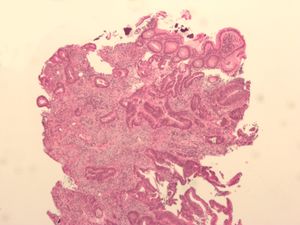

سرطان القولون Colon cancer سرطان القولون الاسم الشائع لانقسام الخلايا على نحو خارج عن السيطرة، في الإمعاء الغليظة. ويفضل العديد من الأطباء استخدام مصطلح سرطان القولون ـ المستقيم، لأن المرض يصيب في الغالب الجزء الرئيسي من الإمعاء الغليظة المعروف باسم القولون، والجزء الأخير المعروف باسم المستقيم. وسرطان القولون ـ المستقيم هو أحد أكثر أنواع السرطان شيوعًا في أمريكا الشمالية وأوروبا، ولكنه نادر الحدوث في آسيا وإفريقيا. وقد يكون هذا التفاوت ناتجًا عن الاختلافات الإقليمية في نوعية الغذاء. فقد أظهرت الدراسات أنه قد يكون بإمكان الناس تجنب الإصابة بهذا المرض عن طريق تناول الأطعمة المخفضة الدهون والغنية بالألياف (وهي مواد تمر عبر الجسم دون هضم). كما تشير دراسات أخرى إلى أن تناول جرعات صغيرة من الأسبرين على الأقل كل يومين، قد يساعد أيضًا على الوقاية من سرطان القولون.